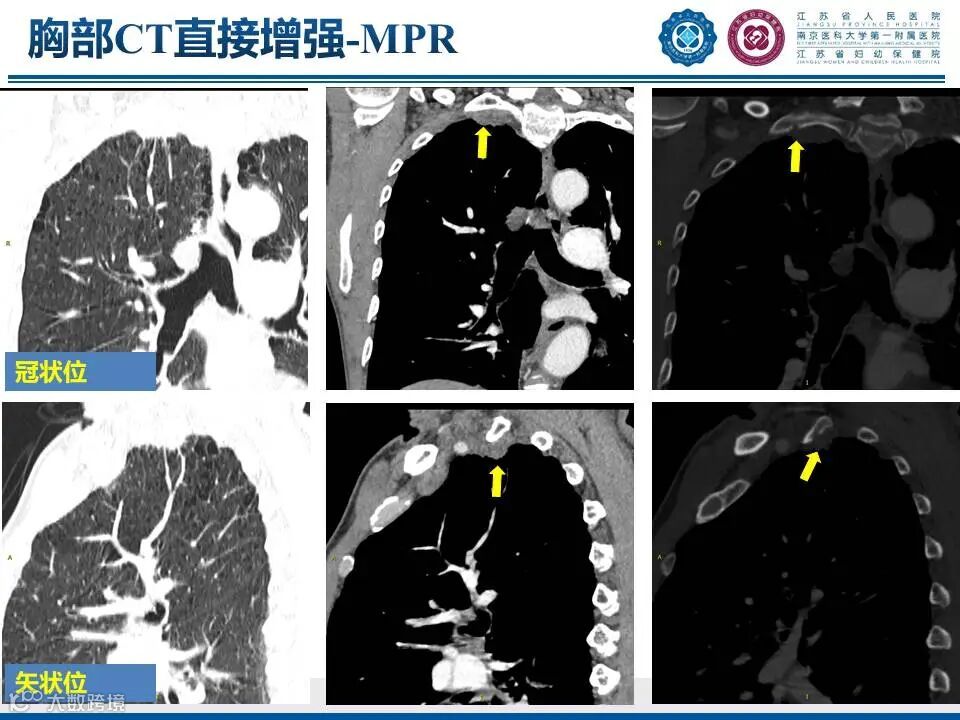

肺上沟瘤

——肩痛背后的致命危机